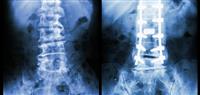

ومن الممكن أن يقوم بالتحقق من علامات التهاب اللثة من خلال الأشعة السينية أو فحص دواعم الأسنان.